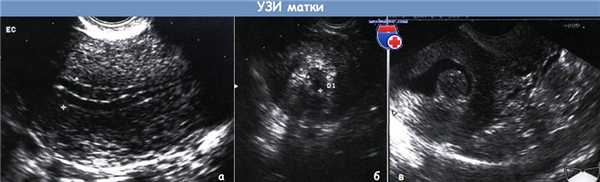

(А) Ультразвуковое изображение матки: тройная линия, указывающая толщину эндометрия.

(В) Ультразвуковое изображение матки: утолщенный эндометрий более 10 мм.

(С) Инстилляция физиологического раствора в полость матки позволяет хорошо рассмотреть подслизистый фиброматозный узел и неутолщенный эндометрий.